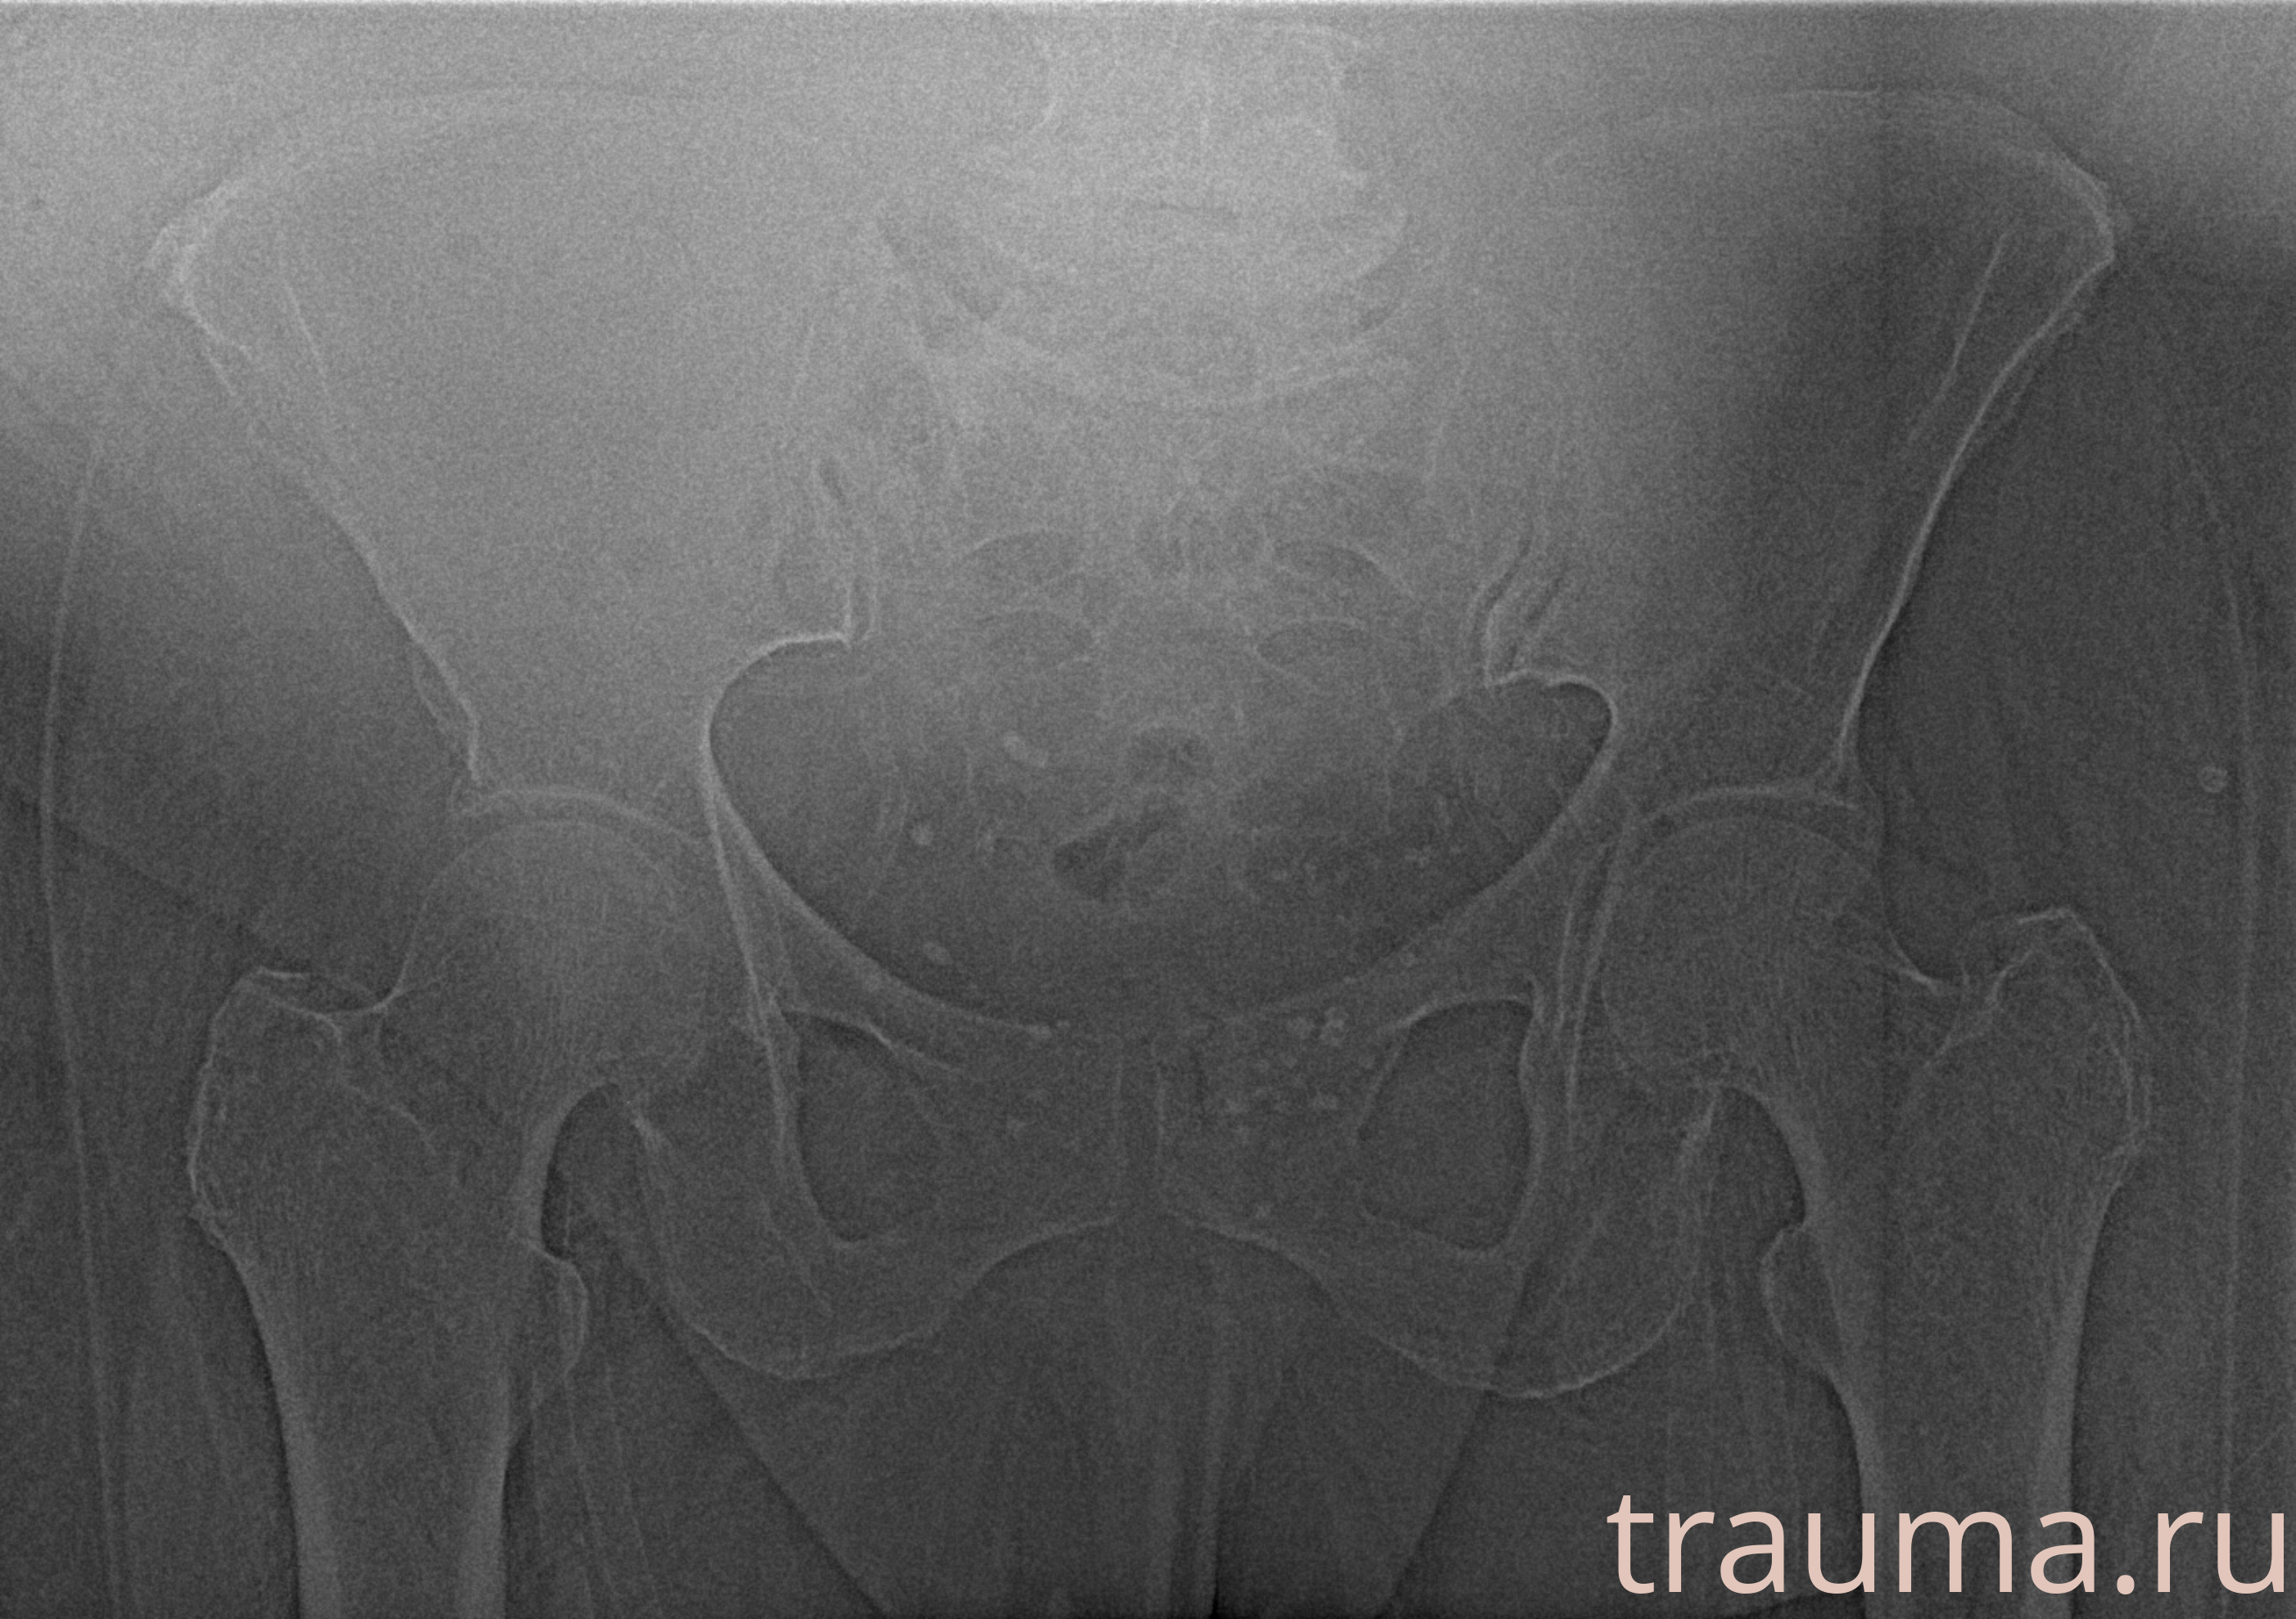

Рентгенограммы

Рентген на дому: по вашему адресу приезжает врач-рентгенолог, травматолог-ортопед с мобильным рентгеновским аппаратом, проводит диагностику травмы или заболевания, делает необходимые рентгенограммы, дает рекомендации по дальнейшему лечению. Получить качественные снимки в домашних условиях возможно благодаря уникальной методике, разработанной МосРентген Центром для института  Склифосовского

при переломе шейки бедра и пневмонии от компании МосРентген Центр - партнера Института имени Склифосовского